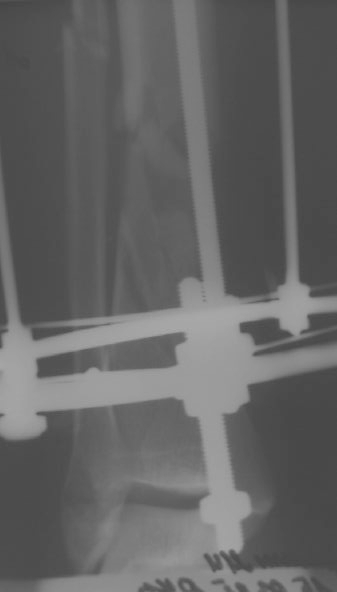

Больному 7 дней назад плита придавила голень стопу. Диагноз Открытый ( 3 б по Каплану) сложный многооскольчатый перелом с выраженным раздроблением н/3 диафиза голени, перелом лодыжек без смещения, перелом основания 5 плюсневой кости с небольшим смещением.

Учитывая, что травма получена в результате придваливания голени плитой, можно расчитывать на проблемы с заживлением мягких тканей. Поэтому, на мой взгляд, конечно удобнее вести больного в аппарате Илизарова. После полного заживления мягких тканей, при необходимости (дефект, действительно, на данных снимках можно только заподозрить), произвести кортикотомию и постепенно закрыть дефект большеберцовой кости. Можно закрыть дефект путем перемещения фрагмента малоберцовой кости на сосудистой ножке, но технически, для меня это сложнее. По поводу комплектации аппарата - я считаю, что лучше зафиксировать стопу, для того, чтобы исключить микроподвижность в области перелома, поскольку дистальный фрагмент достаточно короткий. Лучше перебдеть, чем недобдеть.

Согласен с Вашей тактикой и полагаю, что пластику мягких тканей и чрескостный остеосинтез необходимо выполнить в один этап. По поводу необходимости вмешательства на костной ране сказать определенно не могу - недостаточно информации. В любом случае на положение фрагментов сейчас не обращайте внимания - аппарат должен быть скомпонован так, чтобы обеспечить условия заживления мягким тканям. Поэтому используйте (по ситуации) укорочение, угловую деформацию, ротацию. Единственное ограничение - возникновение сосудистых нарушений от деформации сосудов и нервов. В необходимом положении и стабилизируйте модули прокcимального и дистального фрагментов. Деформацию устраните потом во времени, после заживления мягких тканей.

Больного прооперировал, обработку мягких тканей на голени не стал делать, думаю, некроз по краю швов на голени заживет под струпом (рис 3). На стопе удалил некротические ткани, готовлю ее к аутопластике (рис 2).

На дополнительных снимках итраоперационно видна значительная потеря массы (рис 6 рис 1). Хотя на снимках контрольных после операции вроде дефекта значительного нет. Все же придется, как-то замещать дефект костный на голени, думаю подготовить морально больного к повторной операции костной пластике, после заживления ран.

1. Дождаться заживления ран и через 2-3 месяца после заживления провести свободную костную аутотрансплантацию.

2. Провести остеотомию сегментарную м/берцовой кости напротив дефекта и медленно этот сегмент подвести с помощью спиц в место дефекта. Можно не дожидаться полного заживления ран.